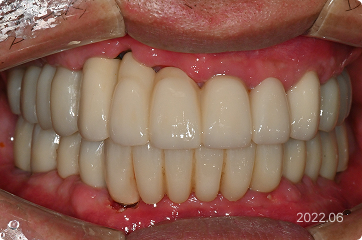

60세, 남 ㅣ중요한 일정 전

“딸이 곧 결혼하는데 그 전에 빨리 치료를 끝내고 싶어요.”

치료 전

원데이 임플란트

치료 후

• 6개월 후 딸의 결혼식 등 중요한 일정 앞둔 상태

• 의식하진정(수면마취) 하 전체 발치,

임플란트 수술 후 원데이 예비 치아 장착

• 발치 , 임플란트 식립 > 최종 보철

약 4개월 내 완성